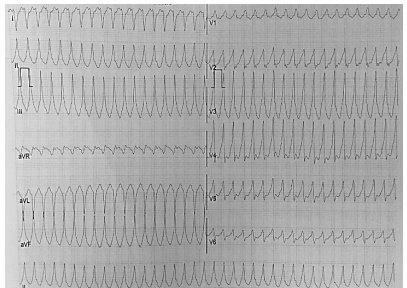

Leia o caso a seguir.

Paciente do sexo masculino, com doença de Chagas, apresenta taquicardia, sudorese, pressão arterial = 76x40mmHg, perfusão lentificada e se apresenta no pronto atendimento com o seguinte eletrocardiograma:

A melhor conduta a ser adotada nesse caso é